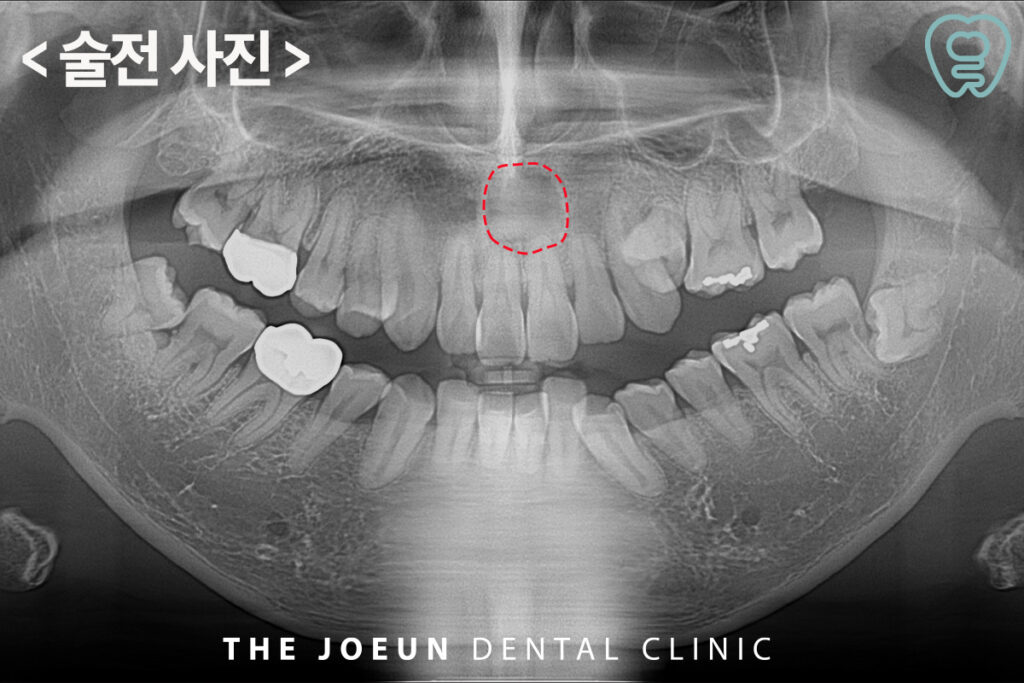

환자분께서는 입천장이 붓는 느낌이 들고 통증이 있다고 하시며 달서구치과에 내원해 주셨는데요. 파노라마를 촬영해 보았을 때, 위쪽 앞니의 뿌리 쪽으로 아주 커다란 물혹이 관찰되었는데요. 더욱 정밀한 진단을 위해 x-ray와 CT 촬영을 모두 진행하였습니다.

모든 방사선 검사에서 경계가 뚜렷이 보이는 낭종이 관찰되었고 낭종적출술을 진행하기로 계획을 수립하였습니다.